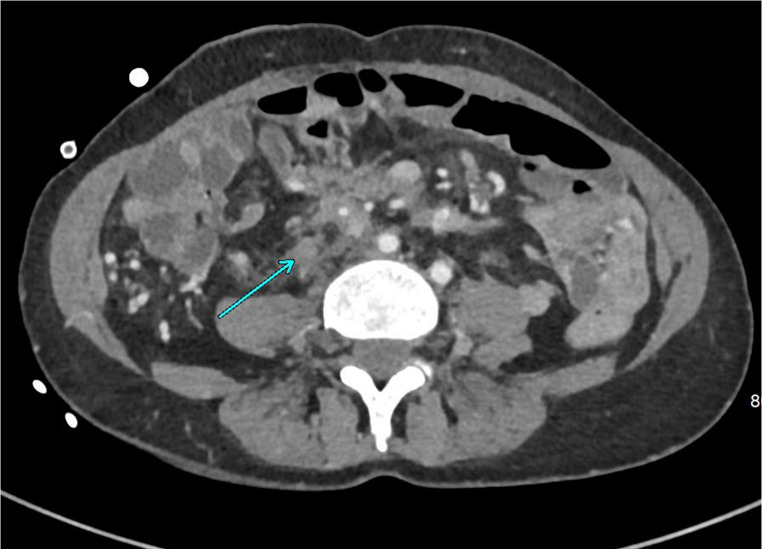

In patients with Familial Adenomatous Polyposis (FAP), large desmoid tumors can develop all over the body. However, the most frequent presentation is as large intra-abdominal masses, usually located in the mesentery of the small bowel. From there, they tend to grow and invade both the abdominal wall and/or the retroperitoneal structures. This can cause life-threatening complications such as recurrent abdominal sepsis with fistulation and damage to vital organs. In selected patients, the only option may be radical resection and replacement by intestinal transplantation (ITx). We aimed to review all the current literature on ITx for FAP-related desmoids and provide an update from the largest single-center experience (2007-2024). All patients undergoing ITx for FAP-related desmoid were included. Between 2007 and 2024, 166 ITx was performed in 158 patients at Addenbrooke's Hospital, Cambridge, UK. Of these, 20 (12%) were for desmoid associated with FAP (10 modified multivisceral transplants, 8 isolated ITx and 2 liver-containing grafts). The five-year all-cause patient survival was 92%, median follow-up was 4.3 years. As the patients presented with very advanced disease, many technical challenges were faced such as: extensive ureteric involvement, abdominal wall fistulation, management of previously formed ileo-anal pouches and extra-abdominal recurrences. Graft selection was another evolving issue, as foregut resection- versus sparing techniques require careful preoperative risk stratification due to increased long-term cancer risk in FAP patients. For certain patients with advanced FAP/desmoid disease, ITx can allow for a radical resection with excellent survival and functional outcomes. However, there is a high degree of initial morbidity associated with the operation and patients should be appropriately counselled. Graft selection and degree of native organ resection requires a careful balanced discussion.

Abstract Image